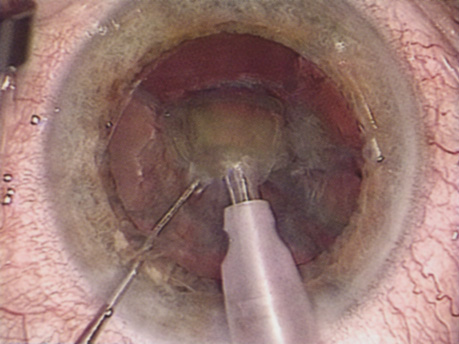

Back to Top